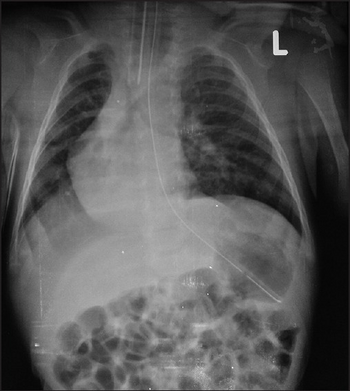

Spinal muscular atrophy with respiratory distress syndrome (SMARD1)- demonstrates eventration of right diaphragm

The diagnosis for DMSA1 is usually masked by a diagnosis for a respiratory disorder. In infants, DMSAI is usually the cause of acute respiratory insufficiency in the first 6 months of life.[2] The respiratory distress should be confirmed as diaphragmatic palsy by fluoroscopy or by electromyography. Although the patient may have a variety of other symptoms the diaphragmatic palsy confirmed by fluoroscopy or other means is the main criteria for diagnosis. This is usually confirmed with genetic testing looking for mutations in the IGHMBP2 gene.[1] The patient can be misdiagnosed if the respiratory distress is mistaken for a severe respiratory infection or DMSA1 can be mistaken for SMA1 because their symptoms are so similar but the genes which are affected are different. This is why genetic testing is necessary to confirm the diagnosis of DMSA.[1]